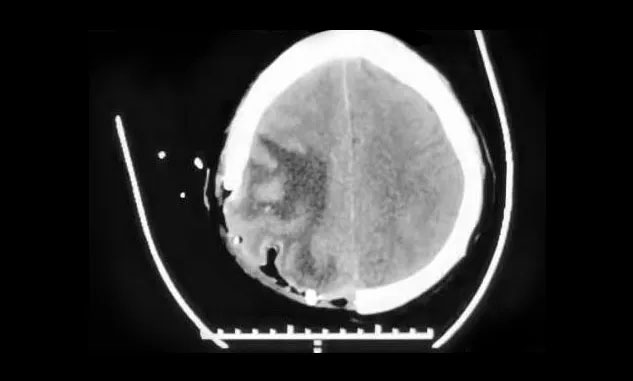

▲ 术后,中线结构恢复正常